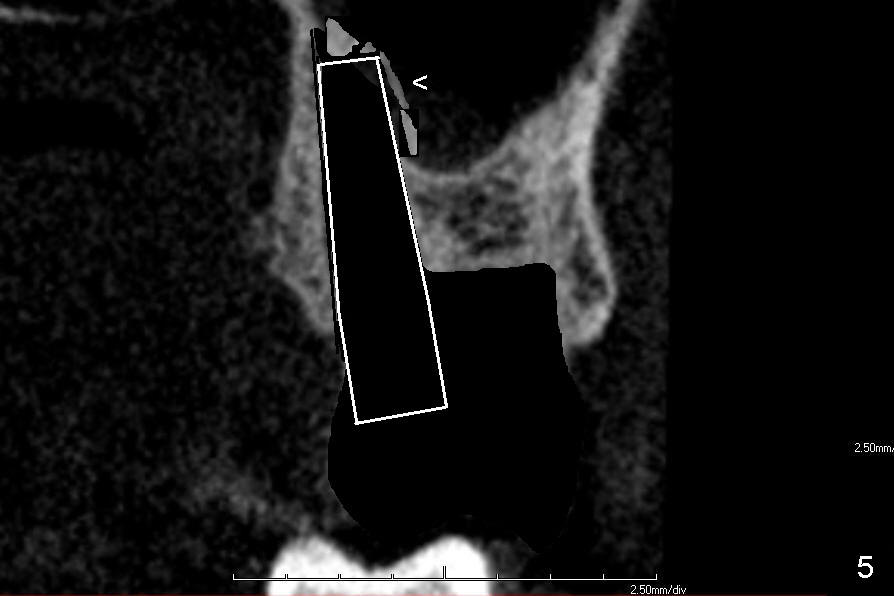

If the septum is small or destroyed by the infection, an implant will be placed in the palatal root (Fig.5), since it is the biggest among these 3 roots (Fig.2). The advantage is that the implant is longer than that placed in the septum (Fig.8). The drawback is that the implant is off center (Fig.5, as compared to that placed in the septum (Fig.8)). The implant placed in the palatal socket is relatively small in diameter. The whole socket will not be occupied by the implant. Collagen membrane will be used to help close the socket as well as bone graft.